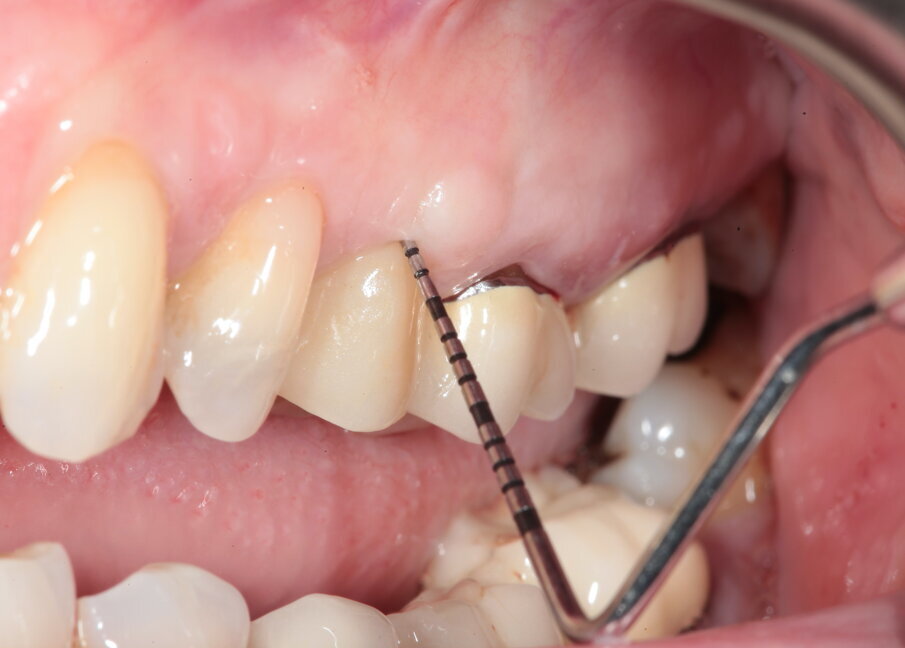

La paziente si presenta in visita lamentando mobilità e l’insorgenza di un dolore alla masticazione a carico dell’elemento 25. Clinicamente l’elemento presenta una corona in ceramica integrale realizzata anni prima (non ricorda quanti) presso altra sede, mobilità di II grado e sondaggio di 9 mm sul versante palatale.

Si presenta inoltre dolente alla percussione. Si riscontra anche l’assenza di risposta al test di vitalità dell’elemento 24, sul quale la paziente riferisce sia stata effettuata una medicazione endodontica da un collega come tentativo di risolvere la sintomatologia dolorosa a carico dell’elemento 25 (Figg. 1-3).